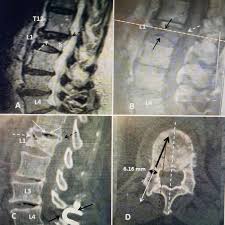

Acute And Chronic Vertebral Compression Fractures Clinical Mri

Acute And Chronic Vertebral Compression Fractures Clinical Mri from clinical-mri.com

Over the weekend i have been experiencing pins and needles in my right hand and arm, a sensation of someone pouring cold water on my left thigh and. The fracture line breaches both the anterior and posterior vertebral body cortex and the anterior superior endplate. A compression fracture is a type of fracture or break in your vertebrae. They often occur in the upper lumbar segments as well, such as l1. In the lumbar region, where the most axial load is, the vertebrae of level l (1 and 2) are injured. Compression fractures are the most common type of fracture affecting the spine. Compression fractures of the spine generally occur from too much pressure on the vertebral body. A compression fracture of a spine bone (vertebra) causes the bone to collapse in height. The doctor suggested bracing for three. Individuals that have been diagnosed with osteoporosis are very prone to developing small fractures in the spine, eventually leading to a compression fracture. The vertebrae are the bones in your back that are stacked on top of each other compression fractures can cause the vertebrae to collapse, making them shorter in height. Apply the one that makes the injury feel better. One and a half years back i got a compressed l1 fracture as a result of a car accident.

I have lumber compression fracture and i want to know how much time i need to rest in bed, currently im having totally bedrest even my wife gives me food by her hand only i standup for toilet so im in very depression and also demotiveted please help me someone does it heal by itself? This collapse can also cause pieces of bone to press on. Fluoroscopic view of a kyphoplasty procedure. In these situations, the fractures. Over the weekend i have been experiencing pins and needles in my right hand and arm, a sensation of someone pouring cold water on my left thigh and. At two months from injury, the fracture is probably still not fully stable as compression fractures take about 3 months to heal. Lumbar compression fractures can be a devastating injury, therefore, for 2 reasons. Are there effective ways to treat a compression fracture with physical therapy? The fracture looks like more of a compression fracture than a burst fracture (there is no retropulsion of the l1 body posteriorly). Anteroposterior and lateral radiographs of an l1 osteoporotic wedge compression fracture. Nonsurgical options include activity restrictions, physical therapy, and treating osteoporosis. Burst compression fracture of the l1 vertebral body is associated with a 35% loss of vertebral body height. Vertebral compression fractures (vcfs) occur when the bony block or vertebral body in the spine collapses, which can lead to severe pain, deformity and loss of height.

First, the fracture itself can cause significant pain, and media gallery. Applying heat in the first few days after an injury draws more blood to the injury site, thus. There is a 3 mm retropulsion into the spinal canal, resulting in only mild canal. Lumbar compression fractures can be a devastating injury, therefore, for 2 reasons. Compression fractures tend to heal completely in about 8 to 12 weeks. More often, the vertebra with a. Vertebral compression fractures | american association of neurological surgeons. Rarely, compression fractures occur in healthy vertebrae as a result of trauma. Anteroposterior and lateral radiographs of an l1 osteoporotic wedge compression fracture. Compression fractures of the spine usually occur at the bottom part of the thoracic spine (t11 and t12) and the first vertebra of the lumbar spine (l1). The fracture line breaches both the anterior and posterior vertebral body cortex and the anterior superior endplate. Apply the one that makes the injury feel better. A compression fracture is a type of fracture or break in your vertebrae.